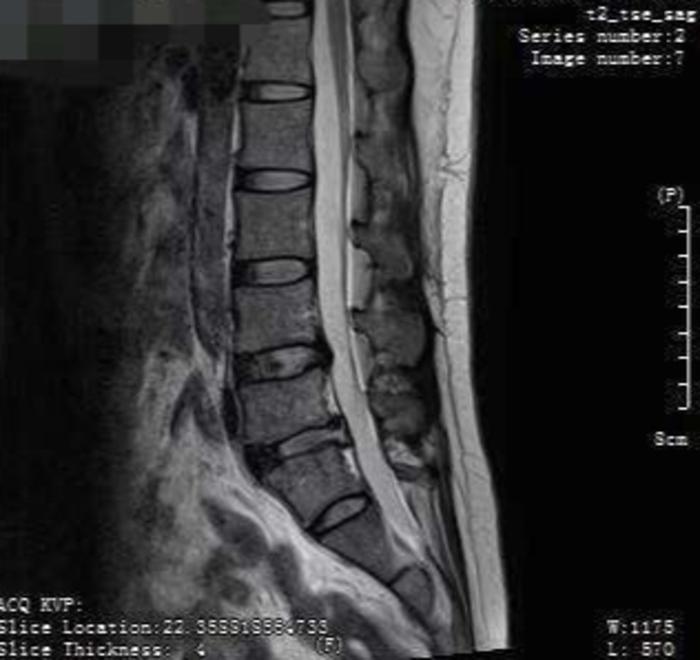

术后脊柱图。

该科主任孟祥玉说,由于突出明显的压迫神经,导致患者产生剧烈腰腿疼,需手术治疗。

入院当日,完善检查后,孟祥玉主刀为患者实施了脊柱内镜下髓核摘除术,手术时间45分钟,创口仅为7毫米,出血量5毫升。

术后6小时患者疼痛明显缓解,可以下床走路,第二天一早就出院回家,入院到出院24小时。